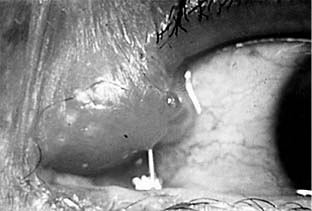

Figure 4-14

Figure 4-14: Acute dacryocystitis.

The chief symptoms of dacryocystitis are tearing and discharge. In the acute form, inflammation, pain. swelling, and tenderness are present in the tear sac area. Purulent material can be expressed from the sac. In the chronic form, tearing is usually the only sign. Mucoid material can usually be expressed from the sac. It is curious that dacryocystitis is seldom complicated by conjunctivitis even though the conjunctival sac is constantly being bathed with pus exuding through the lacrimal puncta. Corneal ulcer occasionally occurs following minor corneal trauma in the presence of pneumococcal dacryocystitis.